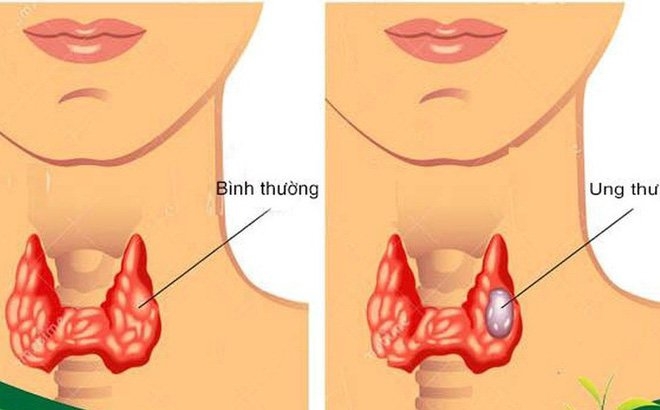

Ung thư tuyến giáp giai đoạn đầu sống được bao lâu?

Ung thư tuyến giáp giai đoạn đầu sống được bao lâu là thắc mắc của nhiều người khi nhận tin mình mắc bệnh. Giải đáp ngay trong bài viết sau!

Triệu chứng ung thư tuyến giáp giai đoạn đầu

Những triệu chứng ung thư tuyến giáp giai đoạn đầu là gì và cần làm thế nào để phòng tránh ung thư tuyến giáp?

Dấu hiệu ung thư tuyến giáp giai đoạn cuối

Dấu hiệu ung thư tuyến giáp giai đoạn cuối bao gồm những gì? Liệu có cách chữa trị nào khi đã tới ung thư tuyến giáp giai đoạn cuối?

Triệu chứng u tuyến giáp ác tính

Triệu chứng u tuyến giáp ác tính bao gồm những gì? U tuyến giáp ác tính có thể chữa dứt điểm khỏi bệnh hay không?

Biểu hiện ung thư tuyến giáp

Biểu hiện ung thư tuyến giáp là gì? Ung thư tuyến giáp có nguy hiểm chết người hay không?

Triệu chứng u tuyến giáp lành tính

Triệu chứng u tuyến giáp lành tính là gì? Khi không may mắc phải thì có thể chữa được không?